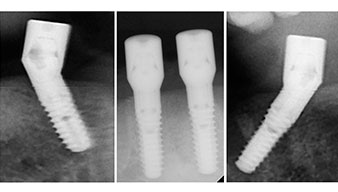

A three-dimensional cone beam computed tomography scan (CBCT, Planmeca) was performed to aid planning and minimize risks. This revealed that the quality and quantity of the available bone were sufficient for the surgery and immediate restoration using the Fast & Fixed method. Following the protocol for this concept, the implants are inserted at 35, 32, 42 and 45. Angling the distal implants by up to 45° shifts the emergence profile to posterior and generates a larger support polygon (Fig. 3).

Fast & Fixed method

Fig. 3

The surgical protocol for the implants employed (SKY, bredent medical) specifies a speed of 1,200 rpm for the pilot drilling (Fig. 7 - 9).

Fig. 7

speed of 1,200 rpm

Fig. 8

Fig. 9

This corresponds to the next preset position in the Implantmed. Here we see the W&H contra-angle handpiece being held at a 45° angle to mesiocaudal in the region of 45 in order to preserve the mental nerve. The mental foramen is used as the anatomic reference for all drilling in this region. The subsequent holes were drilled at a reduced speed of 300 rpm (Fig. 10 and 11).